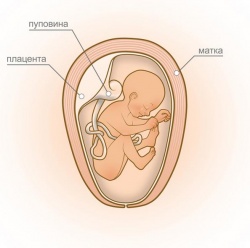

У 24 тижні вага малюка складає 500-600 г, довжина тіла - 29-30 см. На цьому терміні в організмі плода починає синтезуватися гормон росту. Тепер малюк стане набагато активніше додавати у вазі і зростанні, що призведе до швидкого збільшення розмірів живота. Рухова активність плода також буде посилюватися з кожним днем.

Дитина вже здатна розрізняти звуки, що приходять ззовні, і виділяти серед них голоси рідних людей. Малюк однозначно реагує на джерело яскравого світла дуже бурхливими ворушіннями, розрізняє смак і запах навколоплідних вод, сприймає сигнали-відчуття від шкіри. Реагує малюк і на емоції матері, змінюючи свою рухову активність в залежності від ситуації, що склалася.

В кінці II триместру відбувається розвиток вестибулярного апарату плода. Фахівці рекомендують в цей період майбутній мамі більше рухатися, займатися йогою або лікувальною гімнастикою. Чим активніше поводиться жінка, тим швидше маля пристосовується до мінливих умов, і тим простіше буде йому адаптуватися в новому світі після народження.

Більшу частину внутрішньоутробного існування малюк спить. На частку сну доводиться 16-20 годин на добу. Весь інший час дитина вільно переміщається в амніотичної рідини. Сторож Божий малюк заявляє про себе енергійними ворушіннями, які добре сприймаються жінкою на цьому терміні. В середньому майбутня мама може відчути до 10 рухів плода на добу. Ворушіння на цьому терміні відчуваються внизу живота, нижче рівня пупка.

Збільшення ваги на 24 тижні становить 5,5-6 кг. Матка досягає рівня пупка, і животик майбутньої мами стає помітний оточуючим. У цей період на шкірі живота можуть з'явитися розтяжки і пігментні плями. Пупок поступово згладжується і виступає вперед. Після народження дитини пупок повернеться до свого звичного стану.